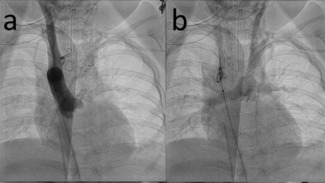

A 3-year-old female presented to our hospital with CHARGE association, tracheoesophageal fistula, neonatal hemorrhagic stroke, and tetralogy of Fallot with a right aortic arch and an anomalous origin of the left innominate artery arising from...